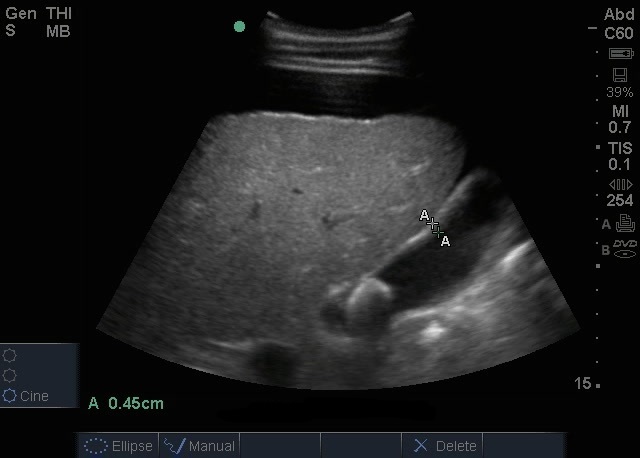

胆囊结石图像

胆囊 (GB) 结石及腹水